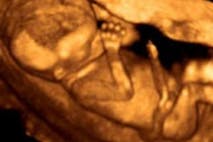

UMN Violating Minnesota’s Fetal Disposal Law?